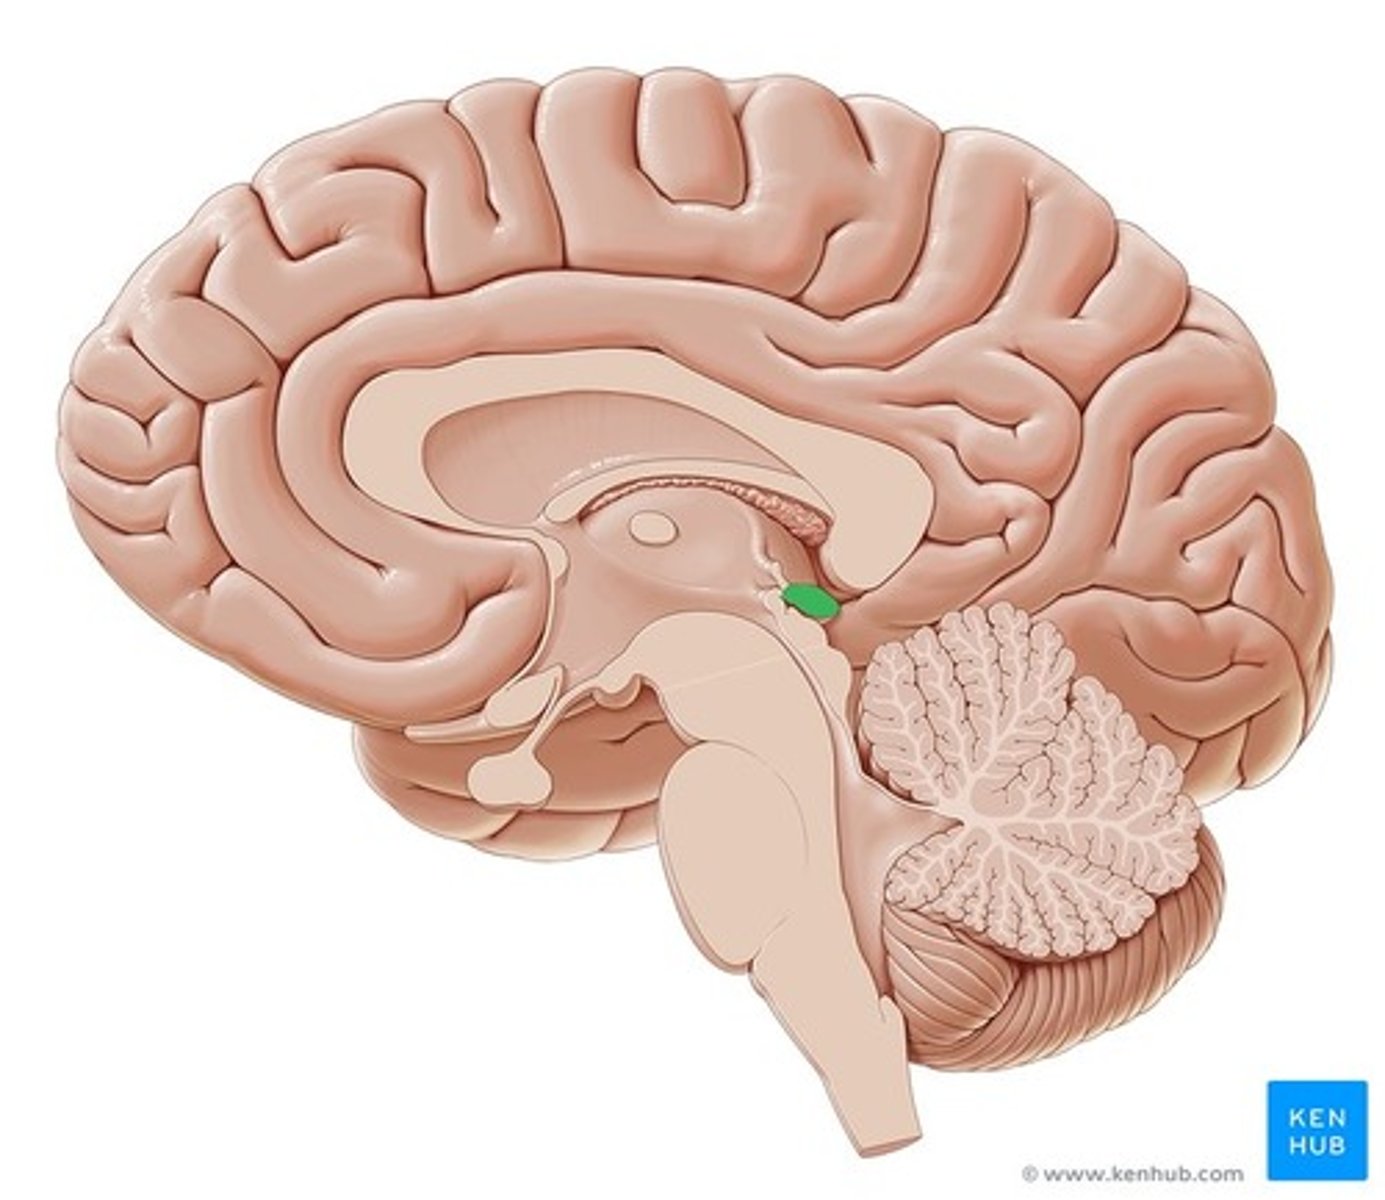

Pineal Body/Gland

Corpus Callosum

Choroid Plexus

Fornix

Thalamus

Hypothalamus

Infundibulum

Pituitary Gland

Lateral Ventricle

Third Ventricle

Fourth Ventricle

Cerebral Aqueduct